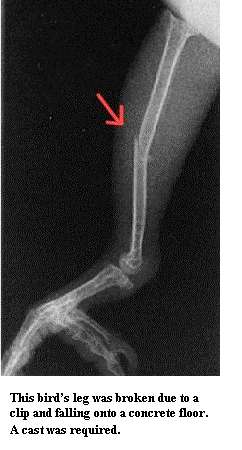

Эта птица сломала лапу, упав на бетонный пол, потому что у нее были подрезаны перья. Этой птице пришлось перенести несколько операций после повреждения киля, произошедшего из-за подрезания перьев. Часть киля была удалена Итак, что мы видим? Разные источники пишут примерно одно и то же, но что стоит за их словами? Подумайте, что на самом деле имеется в виду?